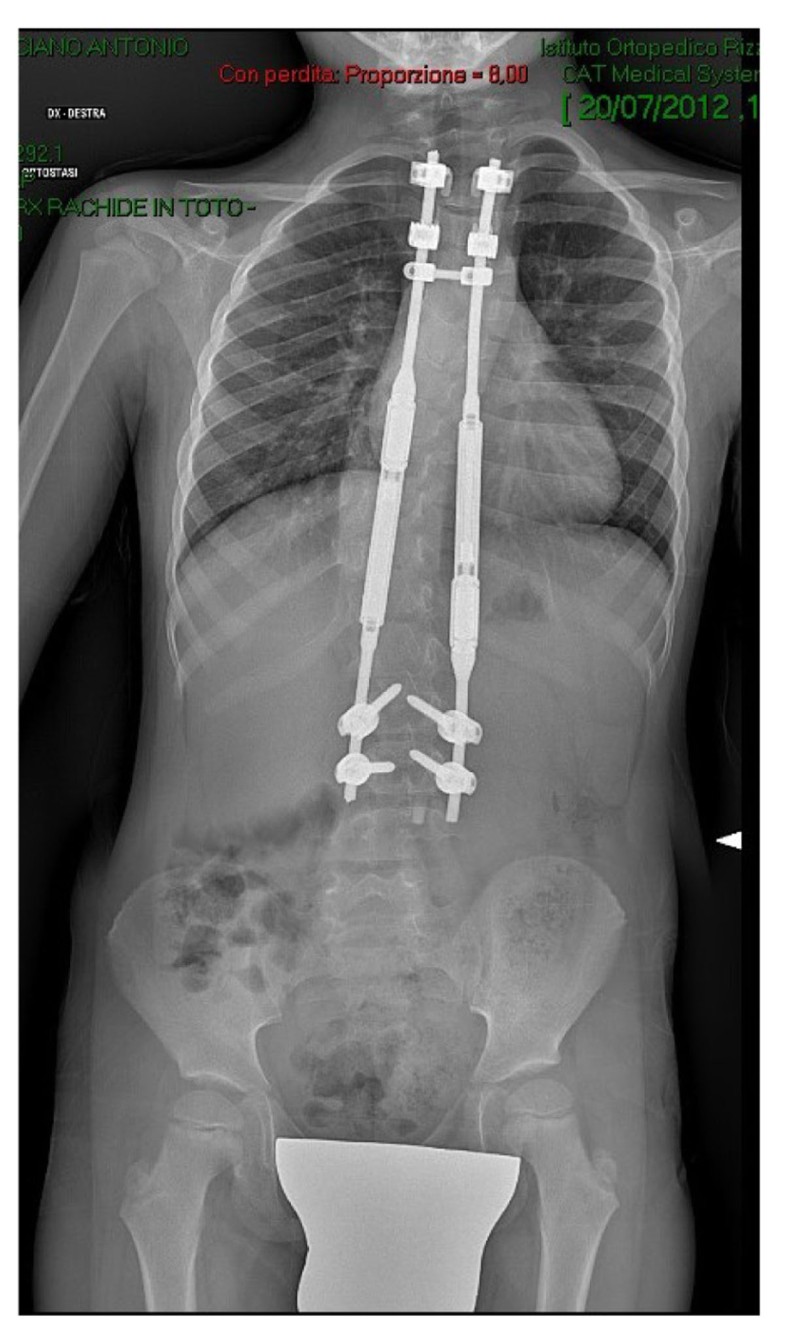

Bioengineering Free FullText Surgical Treatment of Pediatric Magnetic Growing Rod Scoliosis magec growing rods are a new surgical treatment for children with severe spinal deformities that uses implantable rods and. magnetically controlled growing rods (mcgr) have been gaining popularity in. After the initial procedure to implant. Early onset scoliosis (eos) presents in patients younger than 10 years. due to these limitations of traditional growing rods (tgrs), the magnetically. Magnetic Growing Rod Scoliosis.

controlled growing rod in early onset scoliosis Magnetic Growing Rod Scoliosis Early onset scoliosis (eos) presents in patients younger than 10 years. due to these limitations of traditional growing rods (tgrs), the magnetically controlled growing rod (mcgr) system has been developed to allow. magec growing rods are a new surgical treatment for children with severe spinal deformities that uses implantable rods and. magnetically controlled growing rods (mcgr) have. Magnetic Growing Rod Scoliosis.

controlled growing rods for earlyonset scoliosis a 4year Magnetic Growing Rod Scoliosis magec growing rods are a new surgical treatment for children with severe spinal deformities that uses implantable rods and. magec is an evolving magnetically controlled growing rod system for the treatment of eos. After the initial procedure to implant. due to these limitations of traditional growing rods (tgrs), the magnetically controlled growing rod (mcgr) system has been. Magnetic Growing Rod Scoliosis.

controlled growing rods for earlyonset scoliosis a 4year Magnetic Growing Rod Scoliosis magec growing rods are a new surgical treatment for children with severe spinal deformities that uses implantable rods and. due to these limitations of traditional growing rods (tgrs), the magnetically controlled growing rod (mcgr) system has been developed to allow. magnetically controlled growing rods (mcgr) have been gaining popularity in. After the initial procedure to implant. Early. Magnetic Growing Rod Scoliosis.